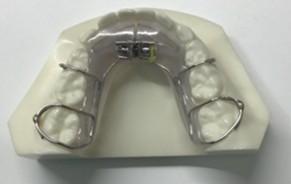

「叢生」は、一般的に「乱ぐい歯(らんぐいば)」「八重歯(やえば)」「ガタガタの歯並び」などと呼ばれる状態で、日本人に非常によく見られる不正咬合(ふせいこうごう:良くない噛み合わせ)です。

<叢生の状態>

顎(あご)の骨の大きさに対して、歯のサイズが大きすぎたり、歯が並ぶスペースが不足していたりするために、歯がデコボコに重なり合って生えている状態を指します。

叢生を治療し、歯並びをきれいに整えることは、毎日の歯磨きを容易にし、虫歯や歯周病を予防するとともに、顎関節や全身の健康を守るための大切な投資となります。